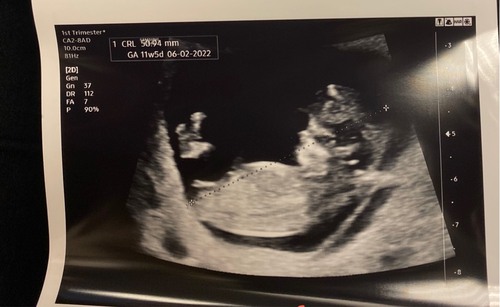

Ik zou zeggen meisje. Ik zie liggend streepje. Ik kon het met onze dochter toen goed zien op de echo van bijna 12 weken. De verloskundige wilde er toen niks over zeggen. Korte tijd later had ik een pretecho en toen dacht de echoscopiste ook aan een meisje. Dat bleek een paar weken later echt zo te zijn bij de geslachtsecho 🤗. Ik weet nog dat de echoscopiste het in haar agenda had geschreven als geheugensteuntje 😜

Vraag me nu af of de echoscopiste expres deze foto heeft afgedrukt om het te laten weten of dat ze die vraag gewoon vaak krijgt. Nog even afwachten!

Jongetje hier en dat stompje was inderdaad duidelijk bij zijn nub te zien. Ook was er al iets wat op beginnende balletjes leek. Dus ik denk inderdaad ook een meisje 🙃